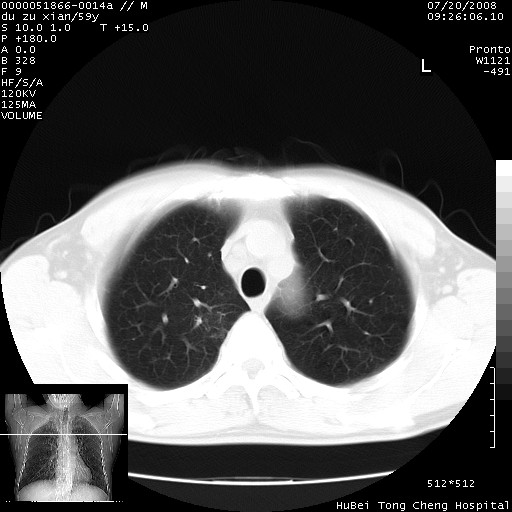

以下是引用宇宙ct在2008-8-25 23:21:00的发言:[br]右肺周围性肺癌并肋骨转移,纵隔淋巴结转移。

以下是引用zsl6918在2008-8-25 22:40:00的发言:[br]右肺周围性肺癌并肋骨转移,纵隔淋巴结转移。

以下是引用zy_zj在2008-8-26 15:24:00的发言:[br]单从病变本身,我倾向良性炎性病变,但肋骨转移了,所以说是考虑右肺周围性肺癌并肋骨、纵隔淋巴结转移可能性大。